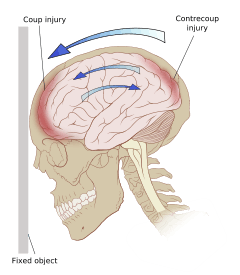

Damage may occur directly under the site of impact, or it may occur on the side opposite the impact (coup and contrecoup injury, respectively).[59] When a moving object impacts the stationary head, coup injuries are typical,[61] while contrecoup injuries are usually produced when the moving head strikes a stationary object.[62]

Even in the absence of an impact, significant acceleration or deceleration of the head can cause TBI; however in most cases a combination of impact and acceleration is probably to blame.[30] Forces involving the head striking or being struck by something, termed contact or impact loading, are the cause of most focal injuries, and movement of the brain within the skull, termed noncontact or inertial loading, usually causes diffuse injuries.[12] The violent shaking of an infant that causes shaken baby syndrome commonly manifests as diffuse injury.[60] In impact loading, the force sends shock waves through the skull and brain, resulting in tissue damage.[30] Shock waves caused by penetrating injuries can also destroy tissue along the path of a projectile, compounding the damage caused by the missile itself.[15]